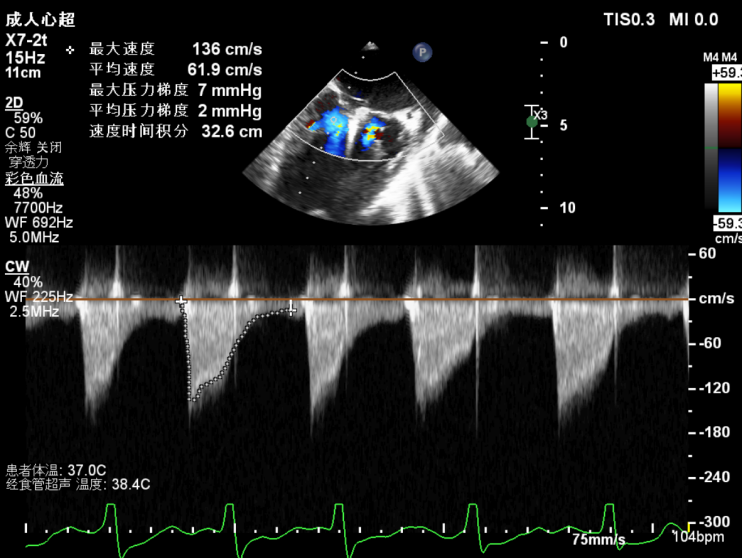

团队在反流最严重的2区精准植入1枚二尖瓣夹,即刻反流下降至微量,血压即刻上升20mmHg,跨瓣压差不升反降,由3mmHg降至2mmHg,改善效果明显,手术仅耗时一个半小时。 这是时隔四年继2020年指导开展区域内首例TAVR(经导管主动脉瓣置换)手术之后,陈茂教授再次带领华西团队,指导开展内自同城区域首例TEER术。陈茂教授对四院心内科心超图像的采集、房间隔穿刺的技巧、手术流程细节的把握、团队的默契配合、术前术后的管理表示称赞,鼓励四院心内科再接再厉造福区域患者。 患者为71岁老年女性,反复出现心累、气促已经超过10年,10多年来心衰的症状逐渐加重,间隔时间越来越短,且近1个月来已经3次因心衰住院,本次住院前已经无法耐受缓慢步行、如厕等日常生活,BNP超过了3000ng/ml。心电图为房颤,心超示左心室明显增大(65mm),重度二尖瓣反流(4+,CarpentierI+IIIb型),射血分数仅为31%。前叶长度:2.27cm且瓣尖增厚,后叶长度:1.14cm且局部钙化,瓣口面积:4.08cm2,反流宽度:1.7cm。患者及家属均拒绝外科开胸手术。 难点: 1.食道超声下该患者房间隔较厚较韧,且粗测高度仅为4.0cm,对穿刺的位置和技巧有较高要求; 2.左心扩大,反流宽度约17mm,放一个夹子可能不能有效解决反流,如放两个夹子需side by side 平行放置,但放置两个夹子有术后狭窄的风险; 3.前后叶对合似有间隙,若选用长宽夹子,会增加瓣叶张力,有瓣叶撕裂的风险,若选用短宽夹子,其捕获瓣叶的难度将增加; 4.患者心功能极差,手术需稳、准、快,不能耐受任何并发症风险。 影像资料 房间隔穿刺